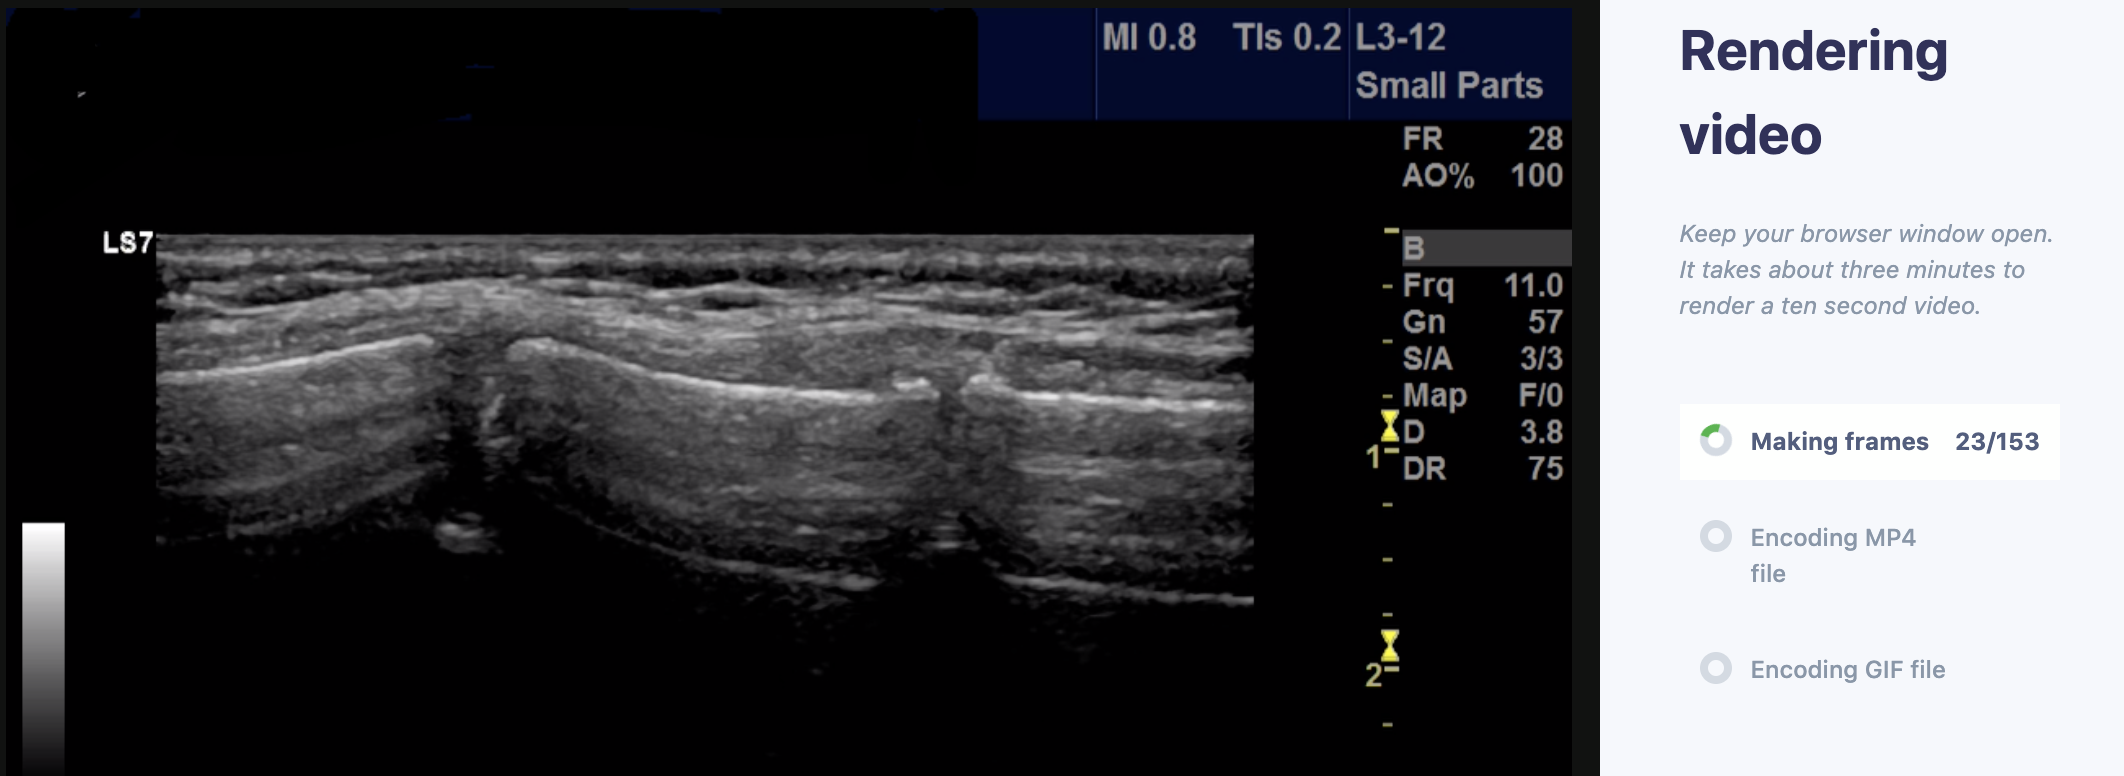

We are excited to announce a new partnership with Ben Smith’s SonoClipShare (@ultrasoundjelly) and David Crockett’s SonoGif (@davycro). You can now share with The POCUS Atlas directly from their sites. SonoClipShare is our favorite website to upload, store, and share ultrasound cases and archives. SonoGif is an incredible tool that allows you to securely and instantly deidenify your clips and convert them to gifs. They have added “Submit to The POCUS Atlas” functions on both sites.